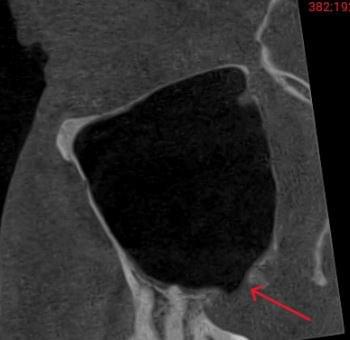

Важливо: Якщо нежить триває понад 2 тижні, з’явилася температура, набряк обличчя чи біль в очах — не відкладайте візит до ЛОРа. Раннє КТ пазух носа дозволяє виявити приховані кісти, поліпи, сторонні тіла або одонтогенний гайморит ще до ускладнень.

КПКТ (конусно-променева комп’ютерна томографія) — це 3D-знімок високої роздільної здатності. На відміну від звичайного рентгену, КТ показує:

ЛОР призначає обстеження у таких випадках: